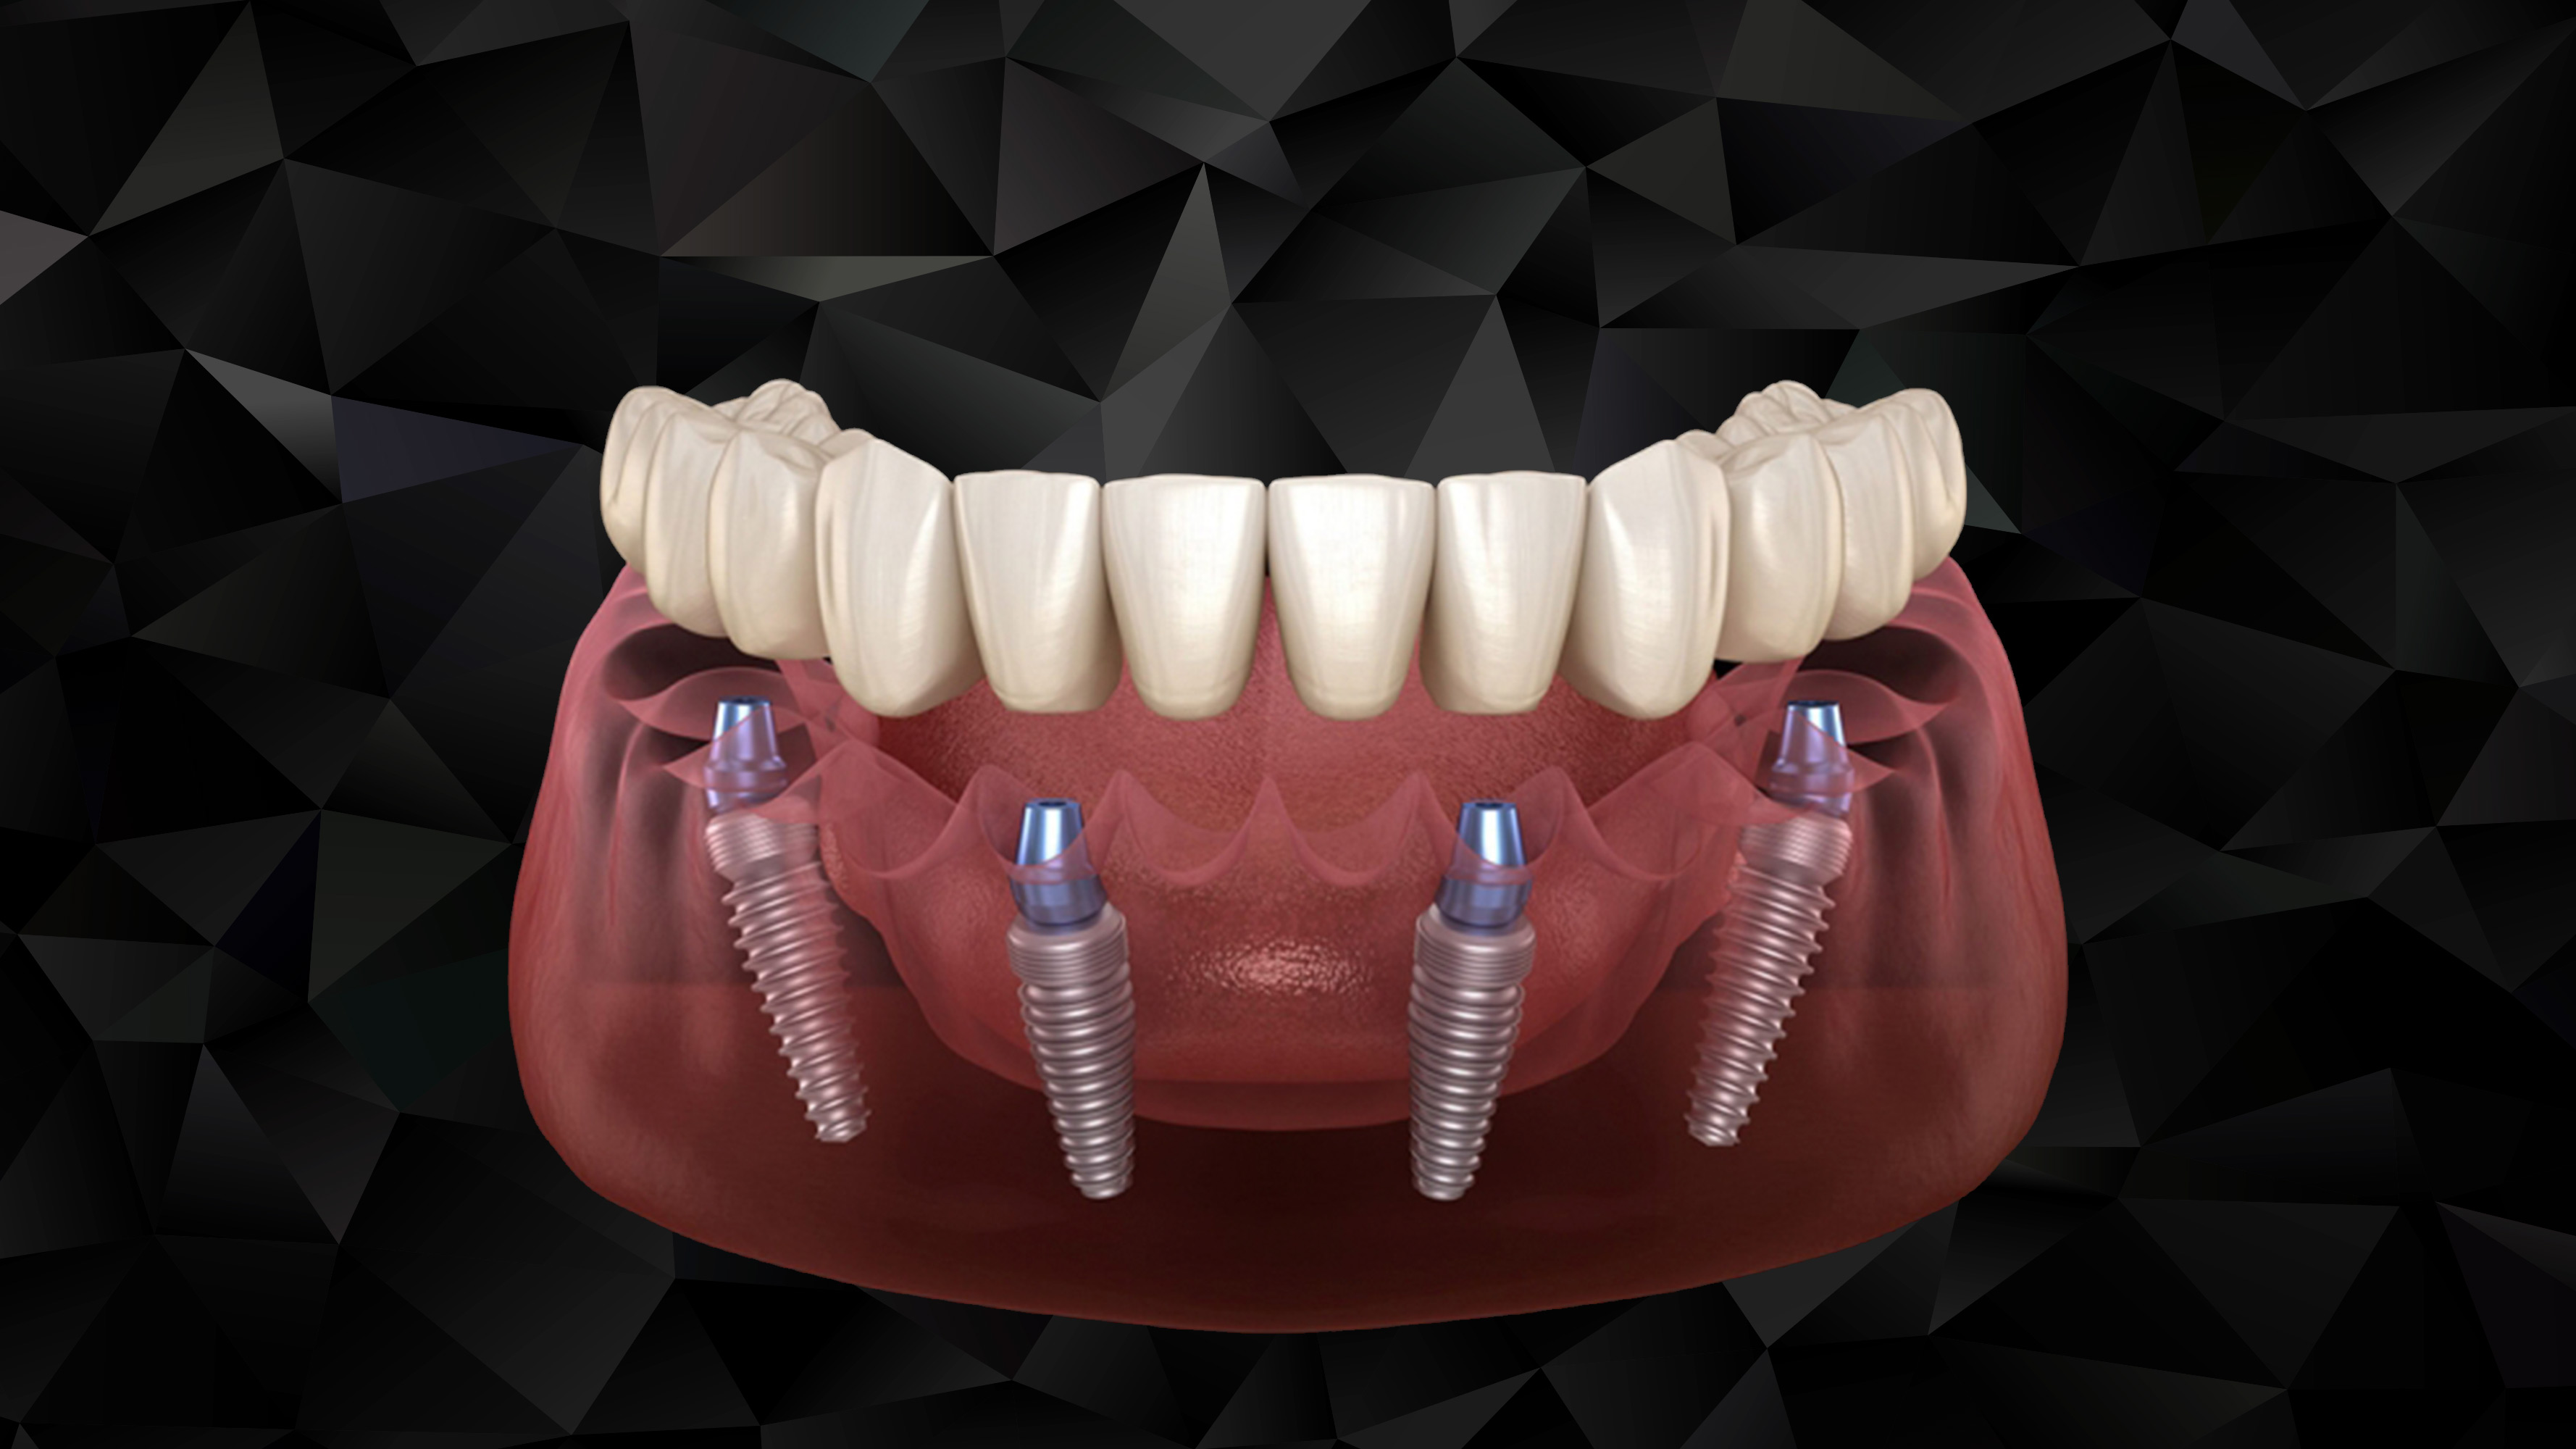

All On Four prosedürü, cerrahi ve protez işlemleri olarak iki aşamadan oluşmaktadır. Tedavi günü hastaya planlamaya uygun şekilde 4 adet dental implant yerleştirildikten sonra aynı gün geçici diş protezi, dental implantların üstüne sabitlenir. 3 ay sonra ise hastaya daimi diş protezleri yapılır.